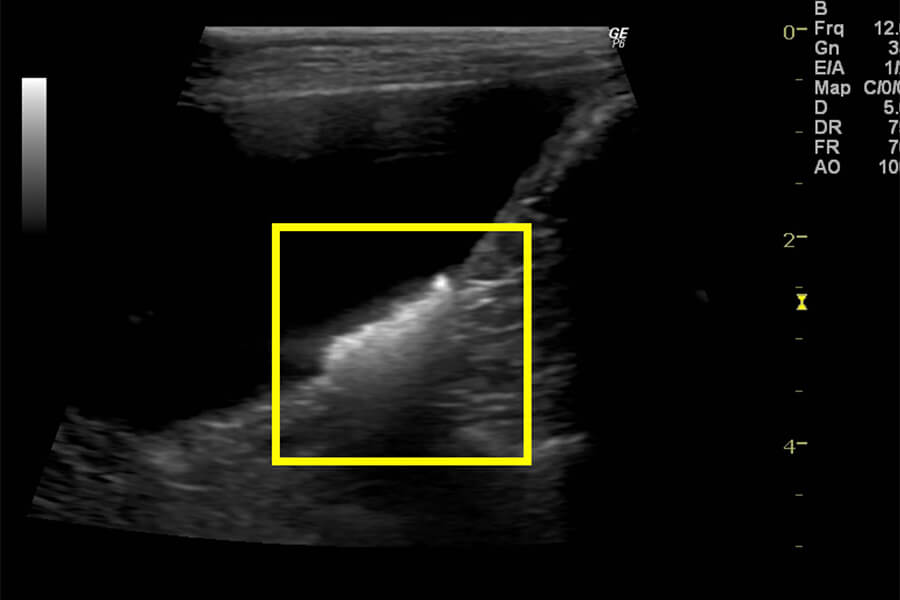

●超音波検査(エコー)

レントゲンでは写らない結石もエコーで確認でき、位置や大きさがわかります。

膀胱結石 エコー